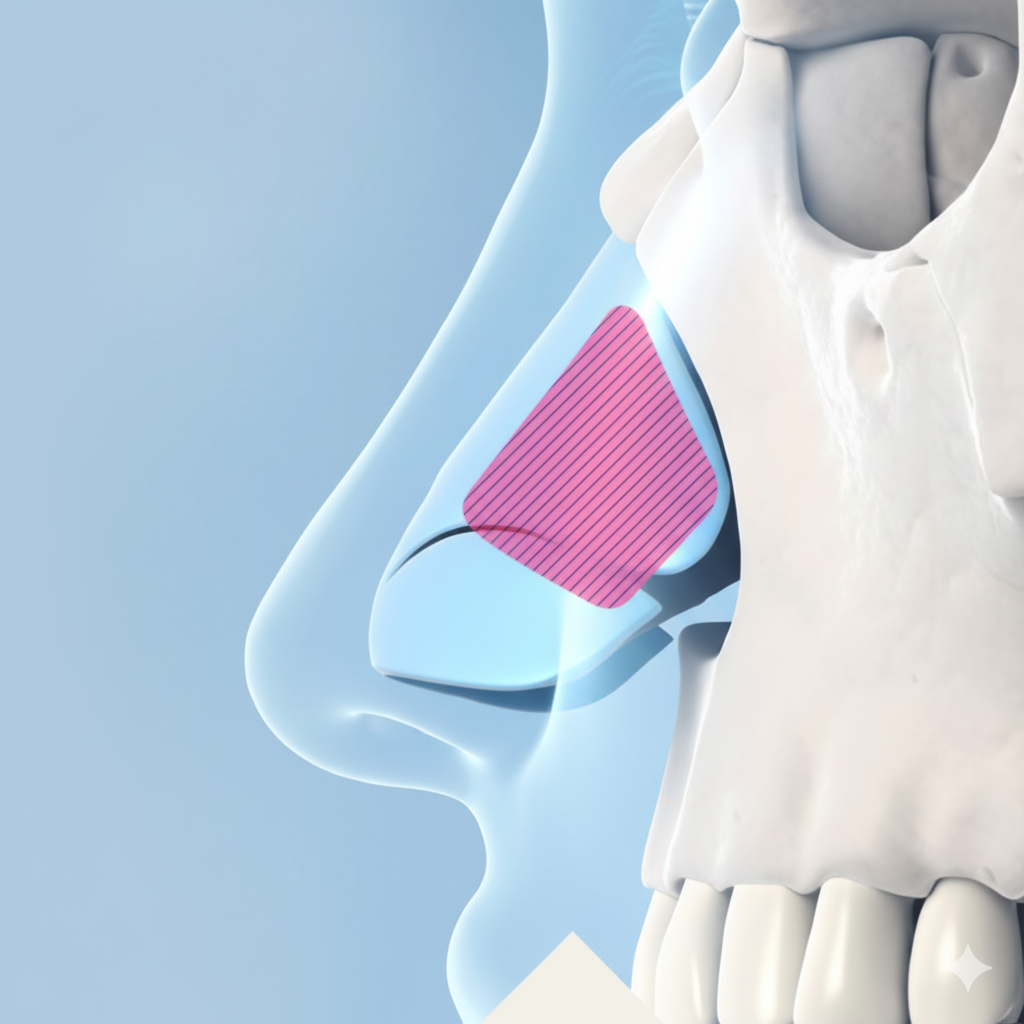

코 끝 높이와 모양 교정 후 콧대와 코 끝 사이에 부족한 공간을 채워 단차 없이 매끈한 코라인을 완성합니다.

코높이보다 더 중요한 건?

단연코 코 끝 라인

단순히 코를 높이는 것이 아닌, 얼굴 비율과 코 끝을 고려해 비순각을 함께 개선하여 이상적인 라인을 만드는 것에 집중합니다.